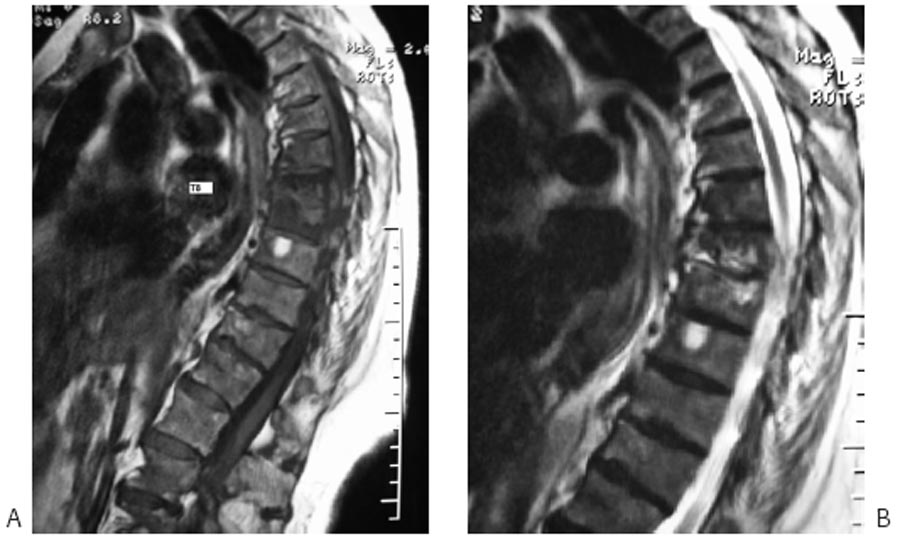

A. En T8 : discrète diminution de hauteur de la partie antérieure du corps vertébral dont le bord antérieur et le plateau inférieur sont flous. B. Deux mois plus tard : ostéolyse du tiers antéro-inférieur du corps vertébral de T8 et pincement de l’espace intervertébral.